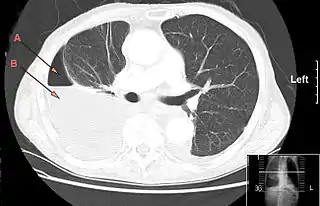

![]() TAC de tórax en el que se aprecia un hidro-neumotórax derecho por empiema pleural. Flechas A: aire, B: fluido | ||